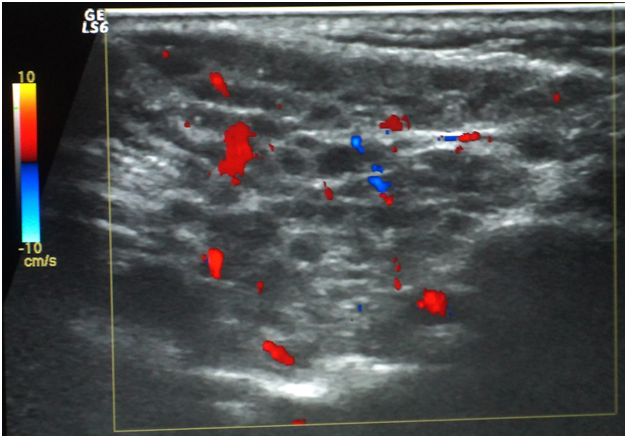

Oral ulcers, especially of the labial mucosa and tongue (Figure 1), were the commonest oral find in GBS while labial numbness, especially in the lower lip, enlarged major salivary glands, and xerotomia were very characteristic of SS. The commonest ocular manifestation in GBS, on the one hand, was intermittent uveitis whose severity ranged from mild to severe while cases of SS have presented typically xerophthalmia. No blindness was reported in the interval of the study as regards cases of GBS. Analogously, no cases of SS did run a transformation course into lymphoma or any other malignancy. Neuro-Behçet involvement and brain aneurysms in GBS, on the one hand, and the follow-up of SS cases, on the other hand, were assessed periodically by MRI. Normal images were obtained in the eighteen cases for this 3-year-old study (Table 1). Sonographically, superficial structures of the head and neck in GBS and SS were assessed. For cases of GBS, a single case has shown a subacute atherosclerosis in the carotid artery but no salient glandular changes were sonographically evident. However, cases of SS revealed a glandular parenchyma of heterogeneous echopattern. There were unmistakable bilaterlal diffuse miliary cystic cavities with patchy calcifications, spotting the underlying atrophic parenchyma. This has overtly promoted a “honeycomb” appearance on the sonograph. No other salient finding could be accentuated (Figure 2).

Figure 2 Sonographic view of parotid gland in SS which displays a heterogeneous parenchyma. The glandular parenchyma exhibits hypoechoic lesions (cystic cavitation) and some calcification foci.There is a conspicuous increase in vascularity on Doppler interrogation.